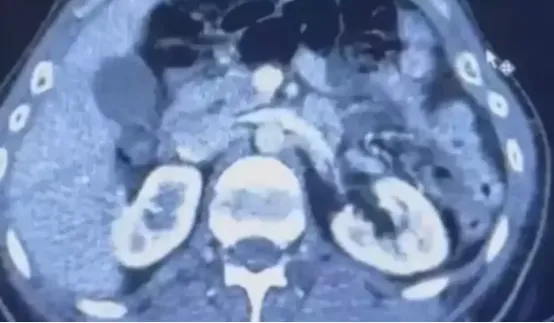

RÖNTGEN ÇEKİLDİ, KAPSÜLLER ORTAYA ÇIKTI

Şüphelilerden S.C. ve R.B.C. muayene edilmek üzere Kayseri Şehir Hastanesi'ne getirildi.

Röntgeni ve ultrason çekilen şüphelilerin midesinde yaklaşık 50 kapsülde 554 gram uyuşturucu olduğu tespit edildi.